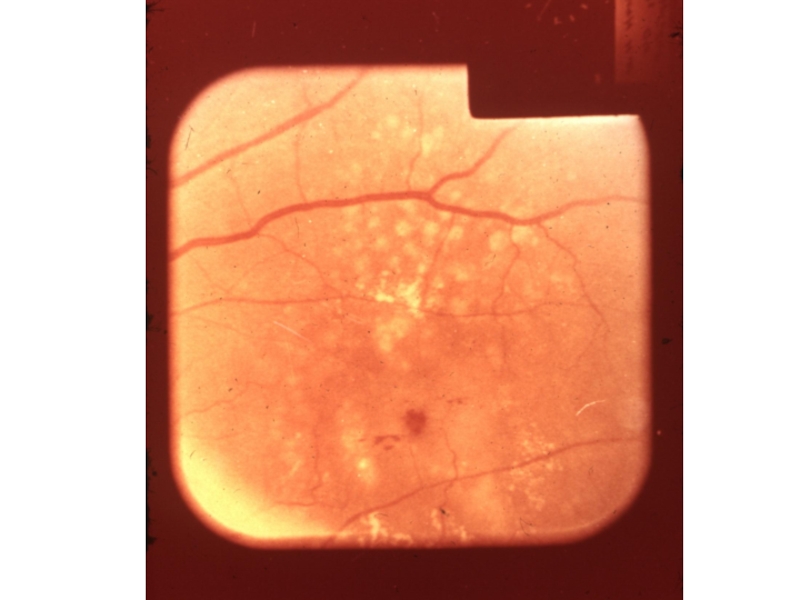

Слайд 323 ст.Гипертоническая ретинопатия:

1. сетчатка мутнеет (отекает) вдоль сосудов;

2. ретинальные геморрагии;

3.

«мягкие экссудаты»-плазморрагии;

4. «твердые экссудаты»-отложение липидов и жиров;

5. в области желтого

пятна «фигура звезды» или «кольца»;

Ретинопатия наблюдается при ГБ 3А-3Б

Слайд 33С-п «серебрянной проволоки», твердые экссудаты

С-п «серебрянной проволоки», твердые экссудаты